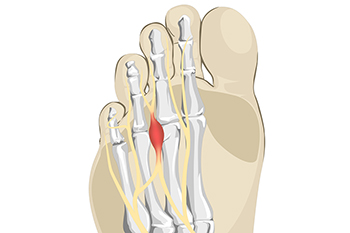

Some people feel the sensation of having a small pebble in their sock or shoe, and this can be a symptom of the foot condition known as Morton’s neuroma. It can develop as a result of wearing shoes that do have enough room in the toe area to move freely in. High heels can fall into this category and can affect women who frequently wear this type of shoe. This ailment affects the nerve between the third and fourth toes and can cause severe pain and discomfort. The nerve can become compressed and irritated, and mild relief may be felt when the shoes that are worn have a wider toe box. This condition will not improve when high heels are consistently worn, and surgery may be necessary to remove or repair the nerve. Patients may find some relief when anti-inflammatory medications are taken and the affected foot is massaged. If you have pain in this part of your foot, it is suggested that you visit a podiatrist who can diagnose and treat Moton’s neuroma.

Morton’s Neuroma

Morton's neuroma is a painful foot condition that commonly affects the areas between the second and third or third and fourth toe, although other areas of the foot are also susceptible. Morton’s neuroma is caused by an inflamed nerve in the foot that is being squeezed and aggravated by surrounding bones.

Morton's Neuroma

Morton's Neuroma, also called Intermetatarsal Neuroma or Plantar Neuroma, is a condition that affects the nerves of the feet, usually the area between the third and fourth toe. Neuroma refers to a benign growth that can occur in different parts of the body. Morton's Neuroma strictly affects the feet. This condition causes the tissue around the nerves that lead to the toes becoming thick, causing pain in the ball of the foot.

This condition can be caused by injury, pressure or irritation. Normally no lump will be felt, but instead burning pain in the ball of the foot will be experienced. Numbness and tingling may also occur. With the onset of this condition, a person may feel pain when tight or narrow shoes are worn. As the condition worsens, the pain may persist for days, or even weeks.

Persistent foot pain should always be a concern. The foot should be examined by a podiatrist if pain persists longer than a few days with no relief from changing shoes. The earlier the foot is examined and treated, the less chance there will be for surgical treatment.

There are some factors that can play a role in the development of Morton's Neuroma. These include wearing ill-fitting shoes that cause pressure to the toes, such as high heels. Also, high impact exercise may contribute to the cause of this condition. Morton’s Neuroma may also develop if the foot sustains an injury. Another cause includes walking abnormally due to bunions or flat feet. This causes excessive pressure and irritates the tissue. At times, people are affected for no determinable reason.

Podiatrists can alleviate the effects of this condition using a treatment plan to help decrease the pain and heal the foot tissue. Depending upon the severity of the Morton's Neuroma, the treatment plan can vary. For cases that are mild to moderate, treatments may include applying padding to the arch to relieve pressure from the nerve and reduce compression while walking. Ice packs can also help reduce swelling. The podiatrist may also create a custom orthotic device to support the foot and reduce compression and pressure on the affected nerve. The doctor will probably advise against partaking in activities that cause constant pressure on the affected area. They may provide wider shoes to ease the pressure from the toes. If these treatments do not relieve the symptoms of this condition, the doctor may use injection therapy.

Surgical treatment may be recommended by the podiatrist if all other treatments fail to provide relief. Normally, the podiatric surgeon will decide on either a surgical procedure that involves removal of the affected nerve or will choose surgery to release the nerve. After examination, the surgeon will decide on the best approach to treat the problem.

Recovery varies according to the type of surgical procedure. The patient will also be instructed on the best shoe wear to prevent the return of this condition, along with changes to workout routines, if this was a cause. Preventative measures are important in ensuring the condition does not return.